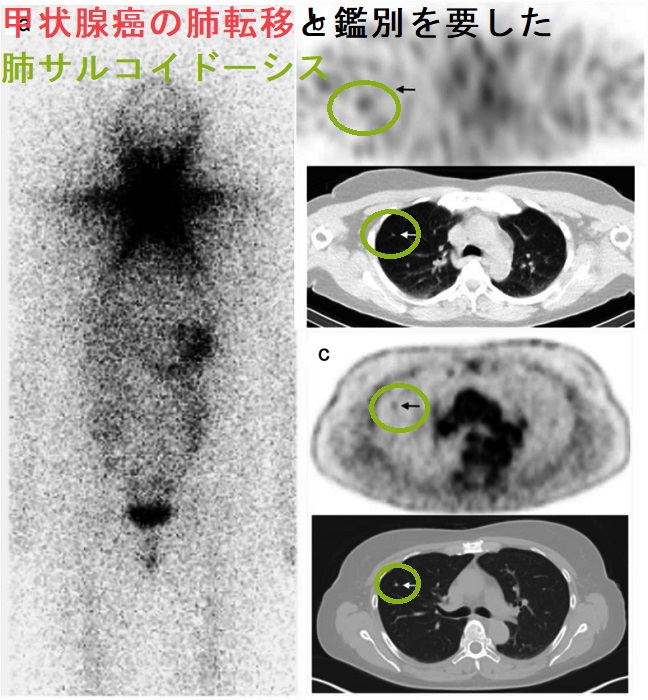

甲状腺癌の肺転移と肺サルコイドーシスの鑑別が必要な場合があります[BMC Cancer. 2021 Feb 7;21(1):139.]。

サルコイドーシスは活性型ビタミンD3への変換促進で高カルシウム血症に。sIL2-Rも高値(甲状腺機能亢進症、悪性リンパ腫でも高値)。サルコイドーシスは細胞性免疫異常で橋本病・バセドウ病、甲状腺乳頭癌合併多い。ステロイド投与で橋本病・バセドウ病も改善。甲状腺サルコイドーシスの超音波エコー画像は甲状腺悪性リンパ腫に類似。穿刺細胞診で甲状腺乳頭癌と診断される場合も。頚部サルコイドーシスは甲状腺乳頭癌リンパ節転移との鑑別要。甲状腺癌の肺転移と肺サルコイドーシスの鑑別が必要な場合ある。眼サルコイドーシスは甲状腺眼症/バセドウ病眼症類似症状。